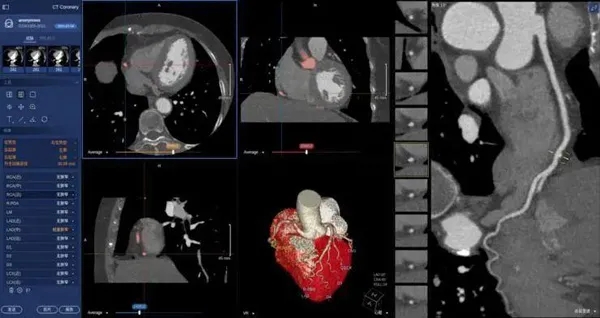

在醫學領域,機器視覺主要用于醫學輔助診斷。首先采集核磁共振、超聲波、激光、X射線、γ射線等對人體檢查記錄的圖像,再利用數字圖像處理技術、信息融合技術對這些醫學圖像進行分析、描述和識別,最后得出相關信息,對輔助醫生診斷人體病源大小、形狀和異常,并進行有效治療發揮了重要的作用。不同醫學影像設備得到的是不同特性的生物組織圖像,如X射線反映的是骨骼組織,核磁共振影像反映的是有機組織圖像,而醫生往往需要考慮骨骼有機組織的關系,因而需要利用數字圖像處理技術將兩種圖像適當地疊加起來,以便于醫學分析。